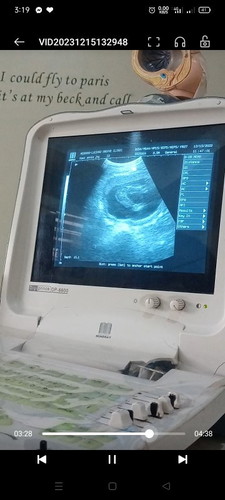

Baby Gender

Im on my 17weeks nung nagpacheck up ako at eto po nakita ni OB sa ultrasound , sabe nya po ay sa tingin nya daw ay GIRL .Sure napo kayang girl base po sa ultrasound ?

hi po 17 weeks nag pa fetal biometry ako ang sabi girl inipit daw kase ni baby ung hita, pero hiwa daw e, wala daw lawit

Nag pa ultrasound din ako nung 17 weeks, hindi pa rin sure. Mas macoconfirm po yan on your 5th or 6th month po.